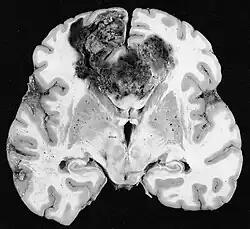

Clinically, VM is diagnosed through immunohistochemistry (IHC) and Periodic acid-Schiff stain (PAS) of patient tumor biopsy. IHC staining identifies the expression of common biomarkers of endothelial cells such as CD31, while PAS staining marks the extracellular matrix for glycoproteins, laminin, proteoglycans, heparin sulfate and collagens, which are known to be a sign of VM.[2] Clinicians diagnose a tumor as having VM by CD31-/PAS+ expressing blood conducting vessels, indicating that there are no endothelial cells but still vasculature present.[2][3]